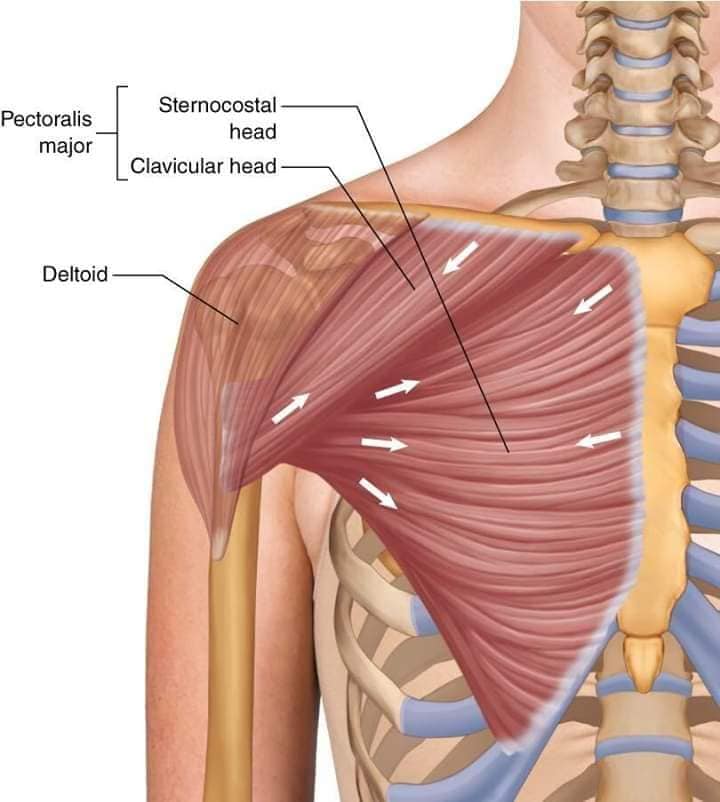

М'язи, що піднімають лопатку: Трапецієподібний м'яз: великий м'яз, що покриває верхню частину спини. Його функція - підтримка і рух лопаток, а також забезпечення стабільності хребта.

М'язи, що ведуть лопатку до хребта: Широкий м'яз спини: великий м'яз, що розташований в нижній частині спини. Він відповідає за рухи плечей і лопаток, а також за розширення верхньої частини тулуба.